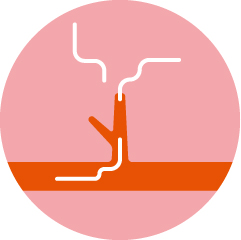

- 5肺に移動

-

一度心臓を通り、肺へ移動。肺に炎症を引き起こします。また、未成熟虫は肺の中でまれに成虫へと成長します。

ねこのフィラリア症から起こる咳などの呼吸器関連の症候群は、HARD(Heartworm Associated Respiratory Disease=犬糸状虫随伴呼吸器疾患)と呼ばれています。